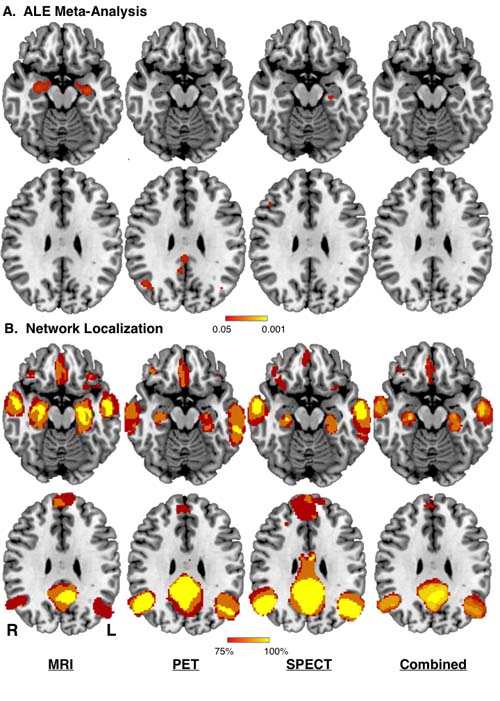

A neural mapping approach that pegs results from more than two dozen previous Alzheimer’s studies found that reproducibility improves when trying to isolate symptoms to a brain network rather than a single area of the brain.

This is the first study to use what the team is calling “meta analysis network mapping” to essentially show results from prior studies that can’t be reproduced to a single location in the brain are mappable to a distributed network, said Ryan Darby, MD an assistant professor of neurology at Vanderbilt University Medical Center, who is first author of the paper that will run in Brain in January.

“The study changes the assumption for where symptoms or cognitive processes should localize – away from a specific region and toward localizing to a brain network. Changing that assumption improves reproducibility,” said Darby.

Neural networks include regions in different parts of the brain that are connected together (akin to distant cities connected by highways), so the study zoomed out its examination to think about symptom-specific circuitry rather than a single spot.

Of the 26 Alzheimer’s studies examined, reproducibility to a specific region came to 20 to 30 percent – a low rate that highlights one of the persistent challenges in studies. But when looking at reproducibility to a network, the rate surged to 100 percent.

The study also found that studies of Alzheimer’s disease patients with delusions localized to the same brain network that Darby found associated with brain lesions causing delusions. In the future he wants these findings and method to shed light on a path to therapy by identifying the symptom-specific brain network.